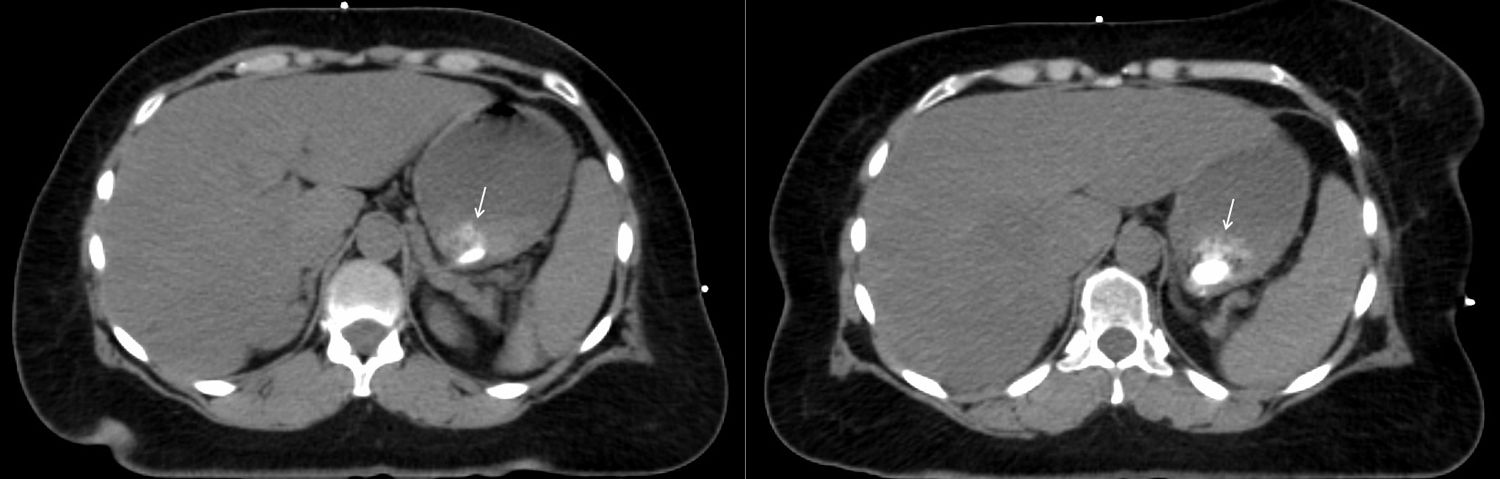

A 57-year-old woman with a history of stage IIB breast cancer (ypT2N1M0) status post neoadjuvant chemotherapy and left partial mastectomy presents to the radiation oncology clinic for CT simulation in preparation for breast radiotherapy. Noncontrast CT scan incidentally found the abnormality depicted with arrows below. What is your diagnosis?

Based on the images shown, what is your diagnosis?